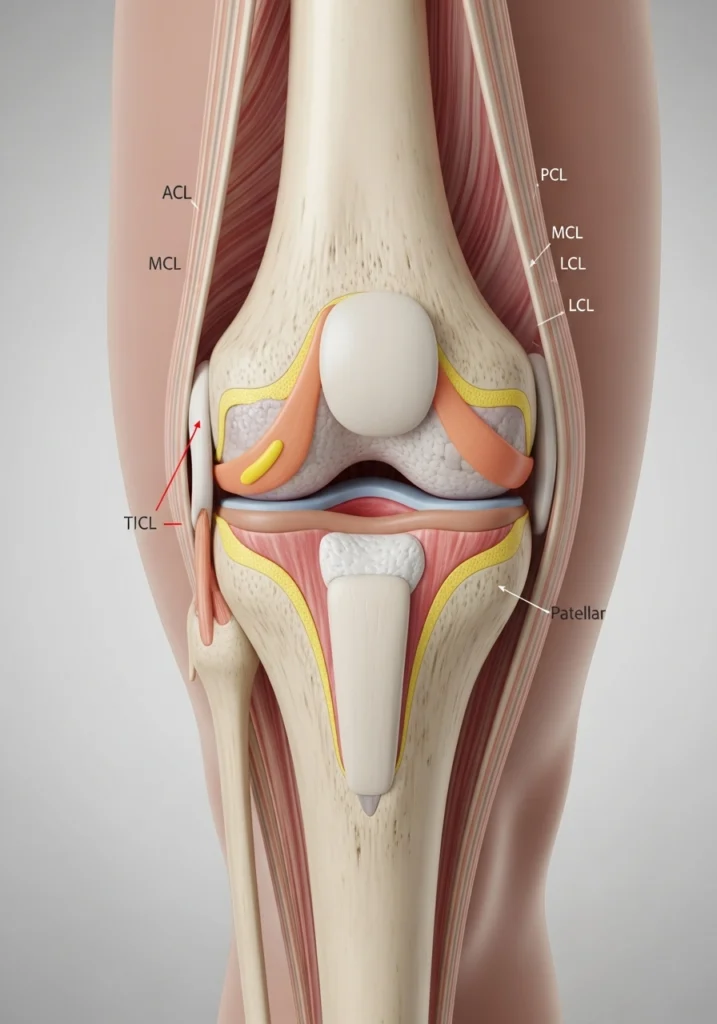

Это связано с тем, что мениск — главный амортизатор колена. После его частичного удаления нагрузка на хрящ увеличивается, а метаболизм синовиальной жидкости изменяется.

Почему артроз прогрессирует после резекции мениска

После вмешательства часть функций мениска теряется. Факторы риска:

• повышенное давление на хрящ;

• изменение биомеханики походки;

• нарушение выработки синовии;

• микровоспаление;

• снижение вязкости жидкости.

Эти изменения могут начинаться уже через 6–12 месяцев после операции.